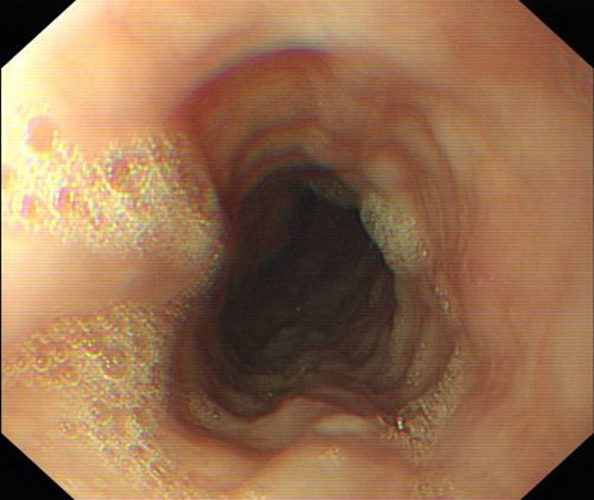

急性胃炎圖片

急性胃炎怎麼辦

急性胃炎

急性胃炎胃部